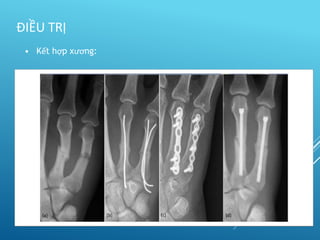

• Kết hợp xương:

– Xuyên đinh

– Vit

– Nẹp

– Bất động ngoài

 Tôn trọng khớp